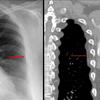

Aortic nipple

Date: 03/29/2014

Views: 5908

Ex 1 CT

Date: 03/23/2004

Views: 5420